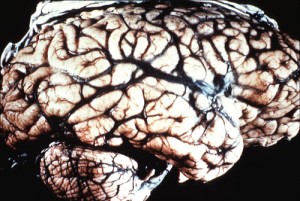

En los inicios de la enfermedad la persona sufre de fallas de memorias, falta de coordinación, perturbaciones visuales y cambios del comportamiento. En la medida en que la enfermedad avanza estos síntomas se van haciendo más severos y se acompañan con movimientos involuntarios, ceguera, debilidad en las extremidades, pérdida del control de la vejiga, infecciones, pulmonía e incluso el estado de coma. Según los especialistas la presencia de la Enfermedad de Creutzfeldt-Jakob ocasiona a nivel fisiológico transformaciones muy singulares en el tejido cerebral ya que éste se llena de pequeños orificios que se asemejan a esponjas. Esto es lo que condiciona la gravedad de los daños cerebrales que se evidencian en la enfermedad.